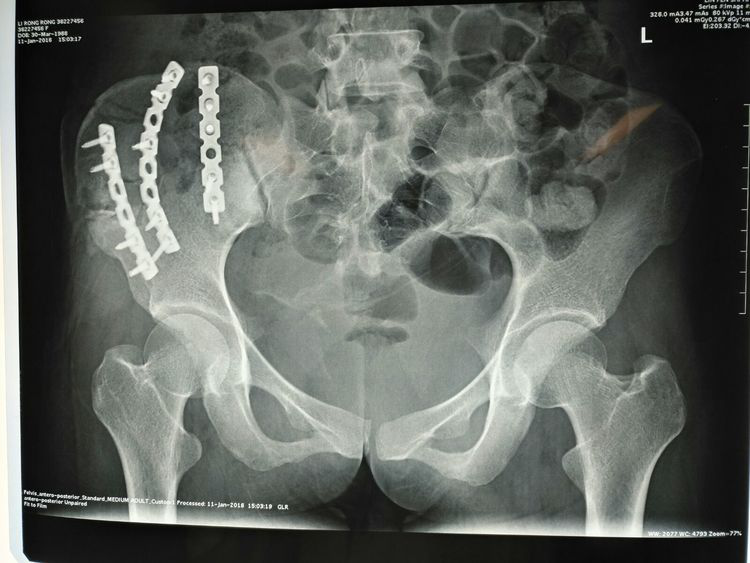

術(shù)后X線檢查